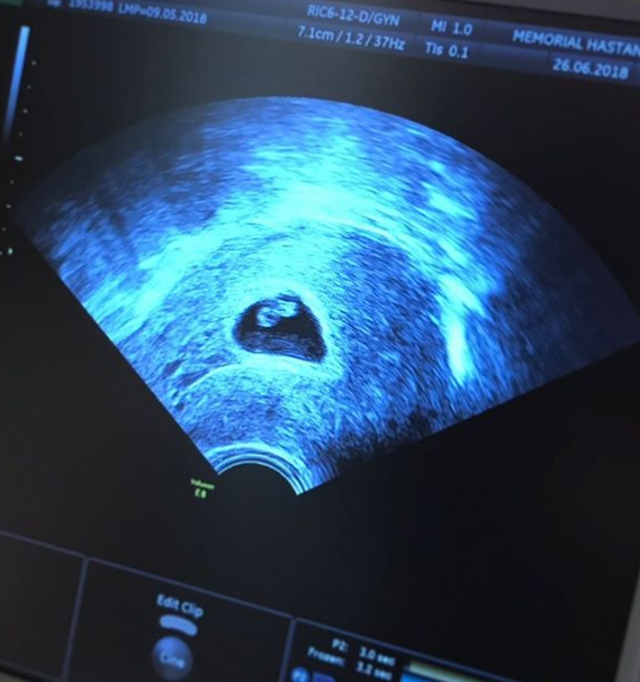

Siren Ertan, bebeğinin ultrason görüntüsünü paylaşıp “O zayıf kalbinden öperim seni ben küçük bezelyem. Kalbin güçlensin bize gel ne olur” dedi.

İşte Siren Ertan'ın o paylaşımı;